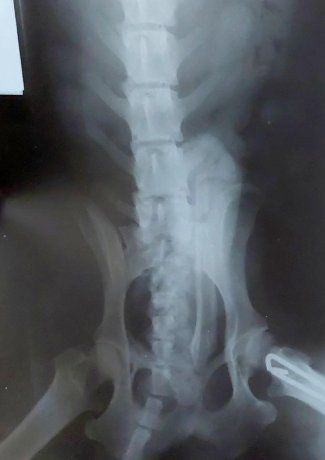

Además compartió que en el expediente 2022-108550205-APN-CFM#ANDIS se pude ver que la auditoría médica expresa: «Radiografía no perteneciente a un ser humano». Finalmente, le pidió al Gobierno por favor «rectificar la información«.